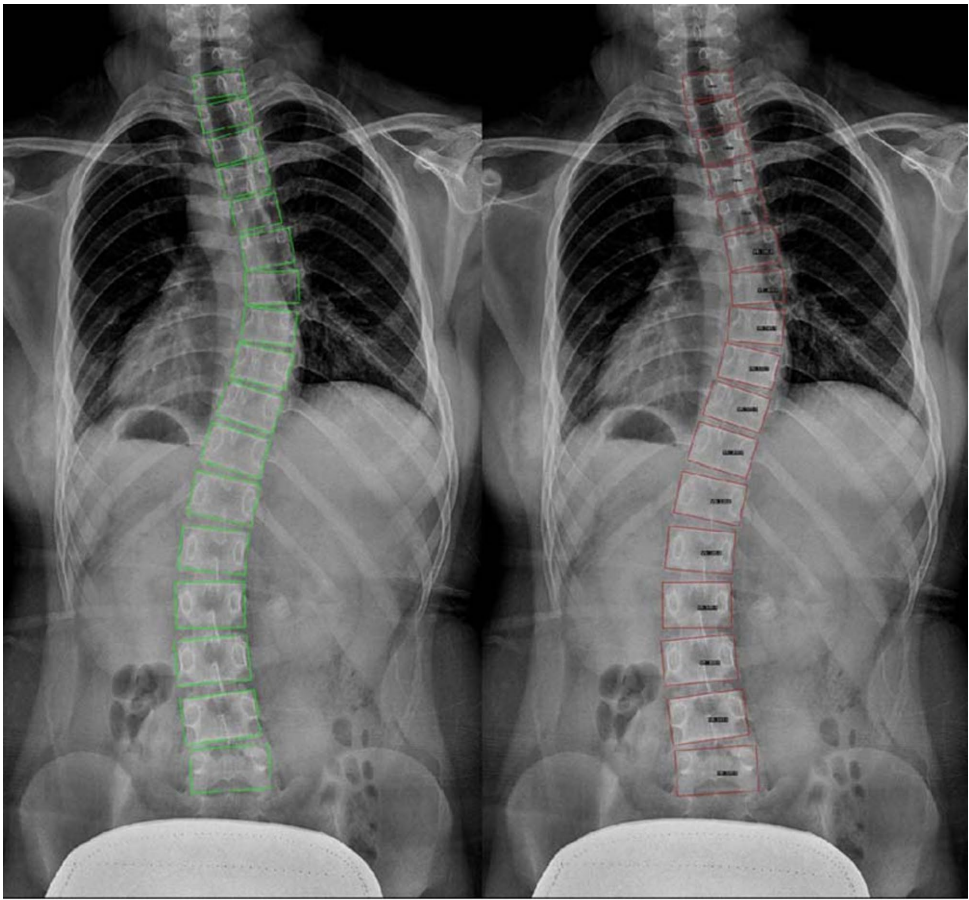

椎体检测结果显示:ReDet模型在验证集上达到0.909的均值平均精度(mAP)和0.999的召回率,绿色标注框与红色预测框的重合度验证了模型的精准定位能力。